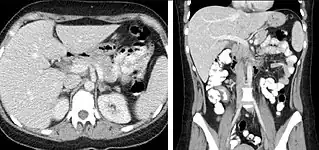

Pancreatic masses

Pancreatic masses are often evaluated using both an early arterial (to evaluate for vascular involvement and thus resectability, figure 9a) and a later "pancreatic" phase (which optimizes pancreatic parenchymal enhancement and thus is best at differentiating pancreatic tumors from pancreatic parenchyma, figure 9b). Pancreatic adenocarcinoma typically is hypoenhancing when compared to the surrounding parenchyma. Most other common pancreatic tumors are hypervascular with avid enhancement (such as pancreatic neuroendocrine tumors) and appear brighter than the surrounding pancreatic parenchyma after the injection of intravenous contrast material.